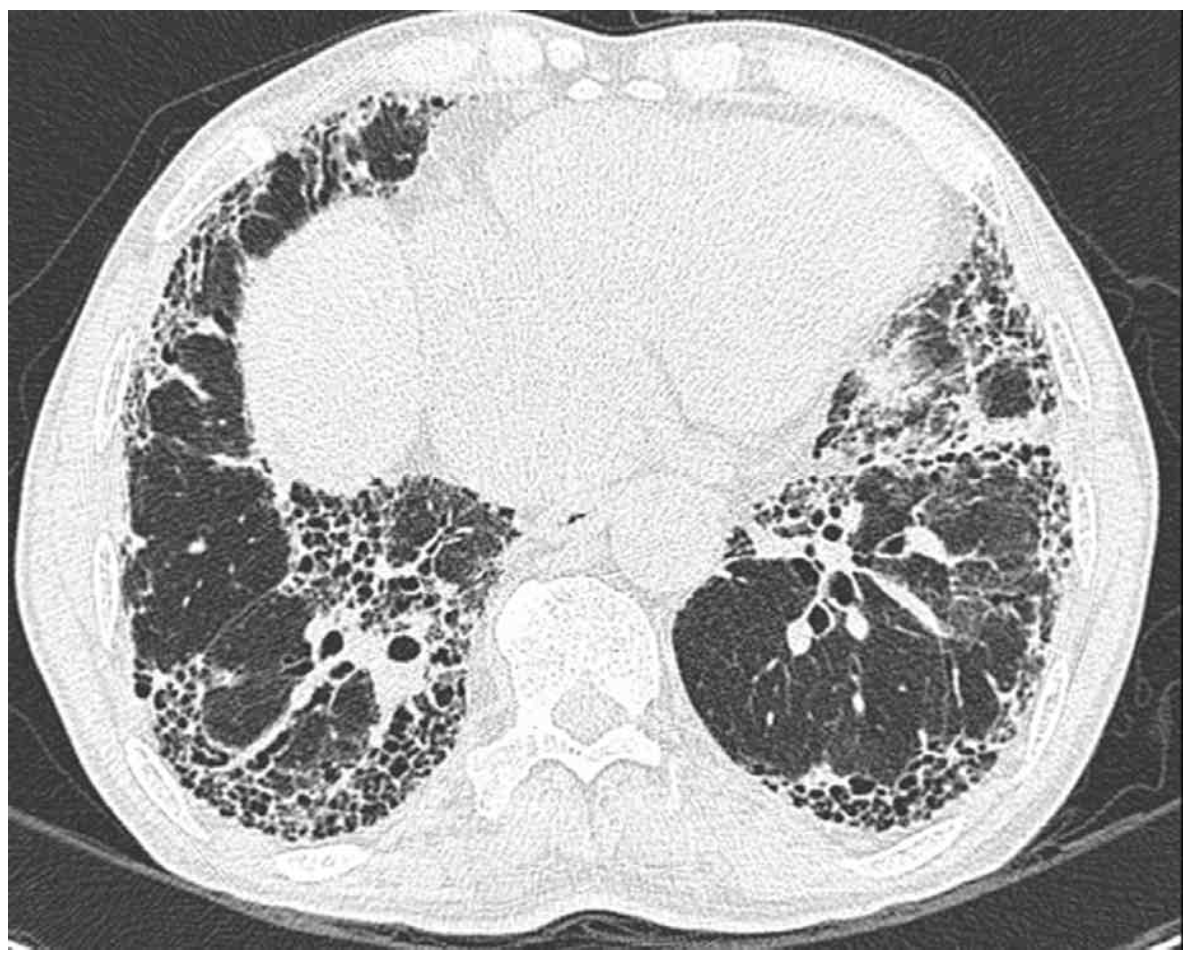

58세 남자가 1개월 전부터 숨이 더 찬다며 병원에 왔다. 6년 전 특발폐섬유증으로 진단되어 항섬유화제를 복용 중이다. 호흡곤란은 최근 3년간 점차 진행하여 최근에는 가만히 있을 때도 숨이 차서 집에서 코삽입관 산소 3 L/분 투여 중이다. 30갑•년의 과거 흡연자이다. 혈압 124/86 mmHg, 맥박 118회/분, 호흡 28회/분, 체온 36.6°C이다. 양쪽 가슴에서 거품소리가 들리고 양쪽 곤봉손가락이 관찰된다. 가슴 X선사진과 가슴 컴퓨터단층촬영 사진이다. 검사 결과는 다음과 같다. 고려할 수 있는 치료는?

CT: UIP pattern

• CXR상 폐 전반에 reticular marking이 증가되어 있으며 자세한 평가를 위해 시행한 HRCT에서 subpleural/basal predominance, honeycombing, reticular abnormality의 통상성 간질성 폐렴(UIP) pattern이 관찰되고 있다. 이는 IPF에서 전형적으로 나타나는 영상학적 소견으로, 환자의 악화된 호흡곤란은 새로운 원인보다는 기존에 진단받은 IPF가 진행함에 따라 발생한 것으로 판단된다.